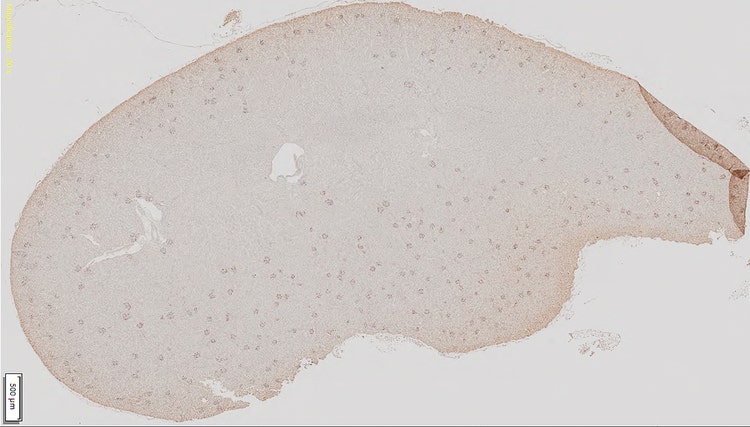

Objektträger (links) eines Nierengewebeschnitts bei 20-facher Vergrößerung mit dunkelbraun gefärbten Glomeruli und (rechts) bei 10-facher Vergrößerung. Es wird deutlich, dass die Glomeruli-Zellen mit der herkömmlichen Schwellenwertmethode (in rot) nicht von anderen Gewebezellen unterschieden werden können.

Bilder mit freundlicher Genehmigung von Zhenhua Miao, Principal Scientist bei ChemoCentryx, Inc. Mountain View, CA (USA)